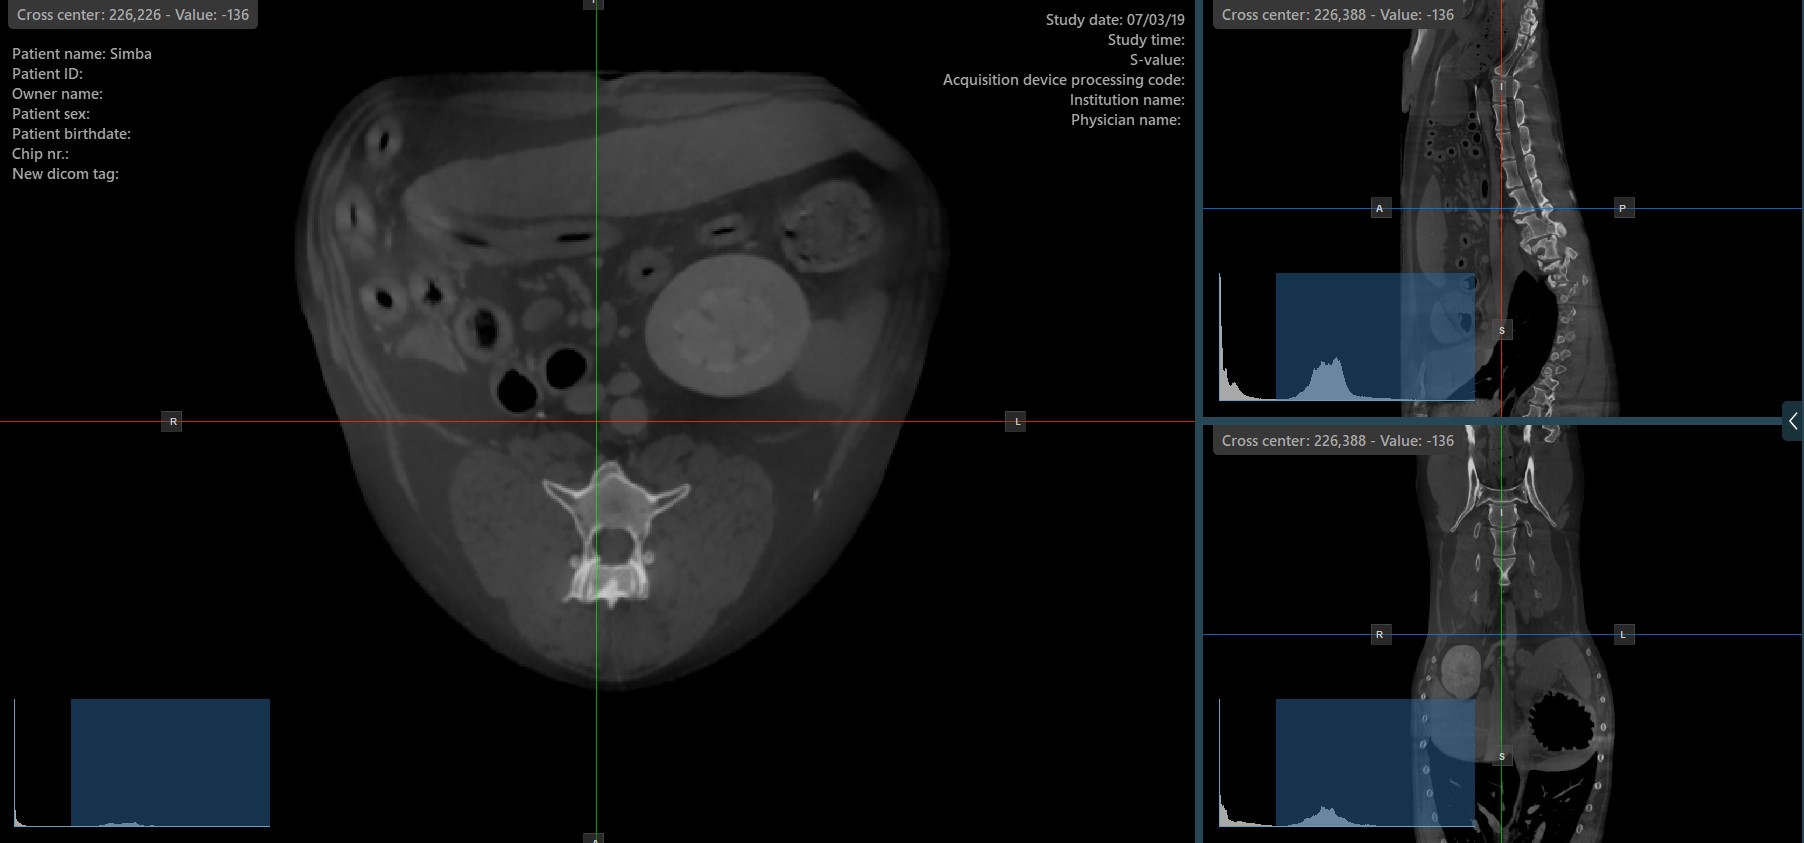

The slicers in MPR view show the intersections and orientation of the three image planes displayed in the active viewports. Users can modify the slicers and change the cross-sectional position of the slices based on the 3D volumetric data.

Each slicers is distinguished by their specific color, which representes the image plane:

• The blue slicer marks the axial plane of the object (perpendicular to the ground)

• The red slicer marks the coronal plane (parallel to the ground)

• The green slicer marks the sagittal plane (perpendicular to the body)